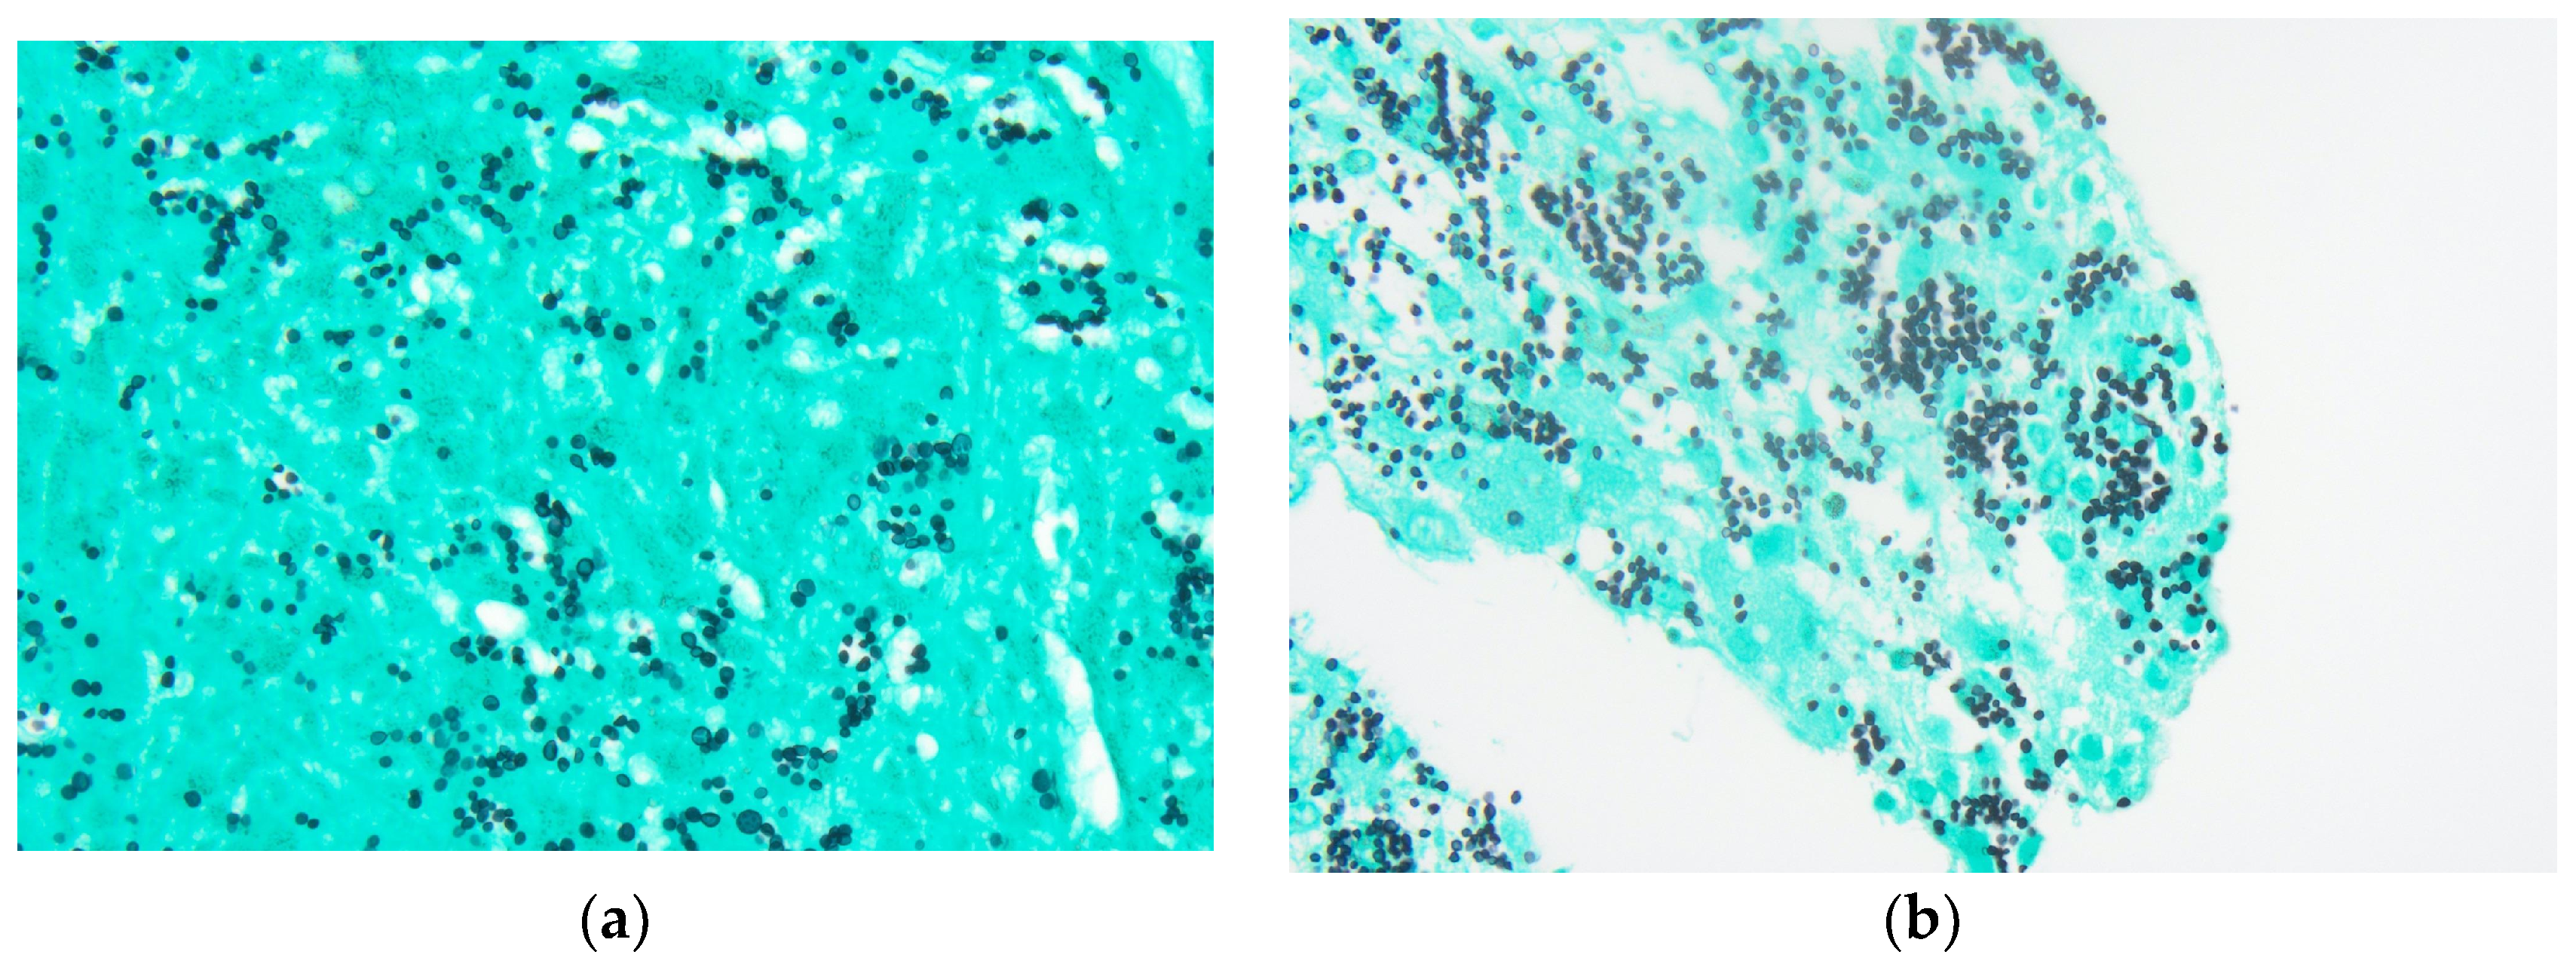

Figure 3. Adrenal mass biopsy: (a) Grocott methenamine silver (GMS) stain, 600× magnification. Organisms show little variability in size and display narrow-based budding; (b) GMS stain, 600× magnification.

The tongue findings prompted a contrasted CT of the neck and soft tissue without significant findings. The patient underwent a punch biopsy of the lingual nodular lesion and a CT-guided left adrenal mass biopsy. Yeast forms compatible with Histoplasma were observed. On the histopathology, fungal organisms consistent with Histoplasma species and necrotizing granulomatous inflammation with elements compatible with Histoplasma were seen involving both the lingual and adrenal masses, see Figure 3, Figure 4, Figure 5 and Figure 6. These findings prompted an infectious disease (ID) consultation. Upon speaking to the family, the patient had reported episodes of confusion prior to admission, therefore, an MRI of the brain with and without contrast was obtained that showed a sub-centimeter enhancing focus within the left putamen/external capsule junction with mild edema.